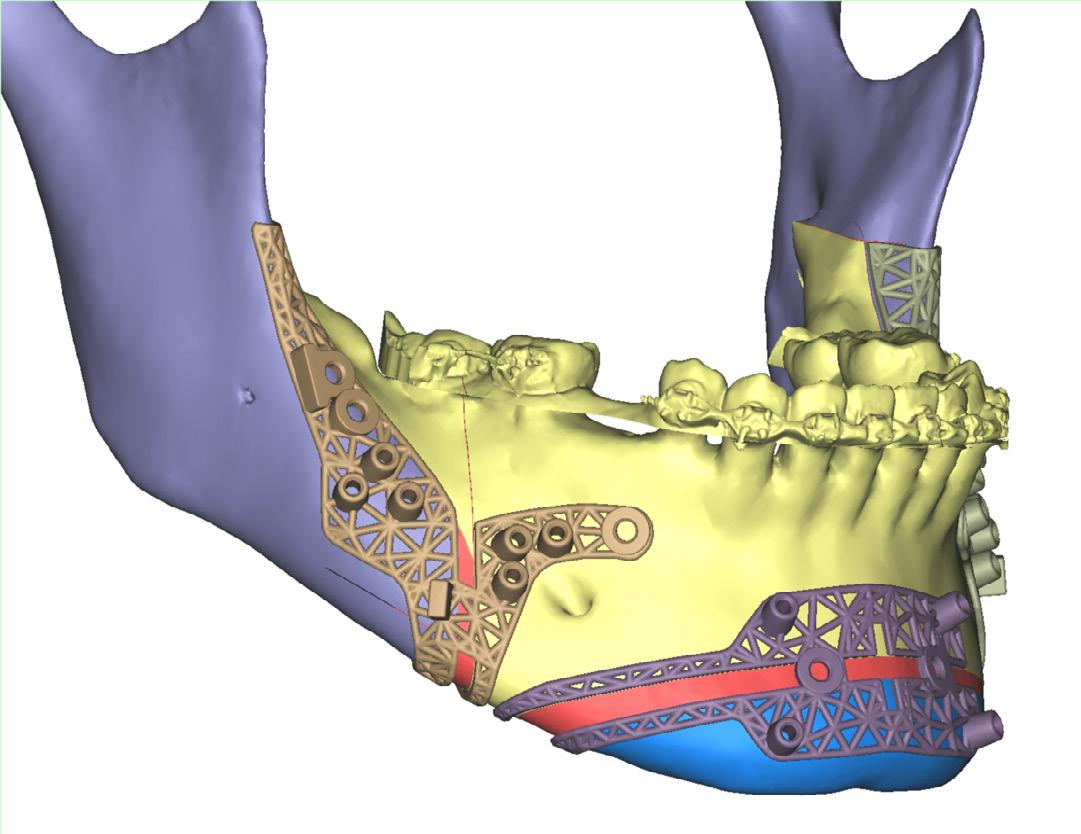

Computer-guided customised treatment of unilateral condylar hyperplasia by proportional condylectomy and orthognathic surgery

Wang D, Smit R, Harrison J and Sealey C

Primary inferior alveolar nerve protection: a CAD/CAM approach

Betar N, Badri D, McCombe A and Finn B